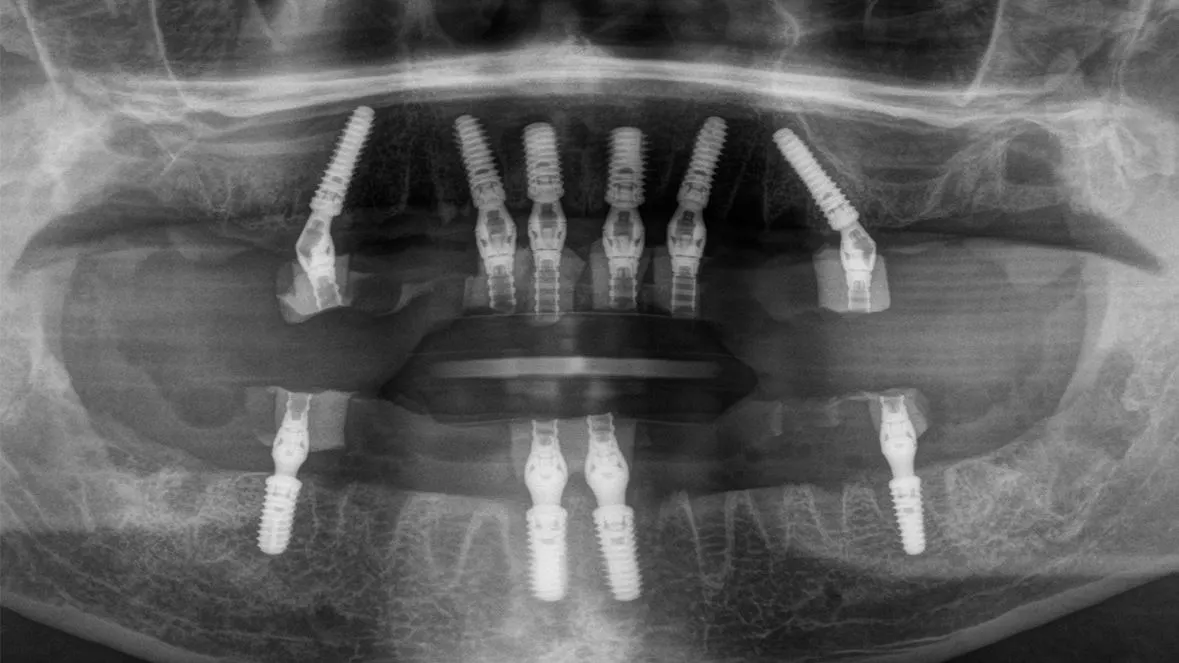

Daher haben sich in der Vergangenheit zum Beispiel Zentren für die Durchführung der Implantatplanung etabliert [6]. Für die prothetisch orientierte Planung benötigt das Planungszentrum neben den Informationen über die gewünschte Position und Anzahl der Implantate und die Unterlagen über das Knochenangebot, die anatomische Struktur und die Bißlage. Diese Daten können über konventionelle Abdrücke oder intraorale Scans der Kiefer, sowie mittels dreidimensionaler Röntgenaufnahmen zur Verfügung gestellt werden (Abb. 1-3). Mit diesen Unterlagen kann dann die Implantatplanung mit Umsetzung einer Navigationsschablone sowie die Herstellung eines Provisoriums erfolgen [4].

Dies erfordert aber gerade beim digitalen Scan eine vollständige Darstellung des Gaumendachs bis zur A-Linie. Im zahnlosen Unterkiefer ist eine Abstützung über den retromolaren Bereich möglich, dieser lässt sich aber je nach Intraoralscanner oftmals nicht vollständig abbilden. Bei einer Sofortimplantation können die Zähne, die nicht durch ein Implantat ersetzt werden zunächst für die Abstützung der Schablone belassen werden. Alternativ hat sich auch die Verwendung von Fixationspins etabliert, mit denen die Schablone auf der Schleimhaut abgestützt werden kann [13] (Abb. 9-10).

im Oberkiefer bei dünner Kortikalis oftmals durch ein festeres Einpressen positioniert werden. Im Unterkiefer wird über die Hülse für den Fixationspin in der Regel eine Vorbohrung notwendig. Nach der genauen Lagesicherung der Navigationsschablone kann dann die komplette Bohrerabfolge geführt bis zur Implantatinsertion angewendet werden. Im Anschluss werden die bei der Planung definierten geraden und angulierten Abutments eingesetzt und die Titanzylinder für das Einkleben des Provisoriums fixiert [1]. Nach dem Einkleben der Zylinder in das Provisorium muss diese nochmals ausgearbeitet werden und die Sofortversorgung ist abgeschlossen (Abb. 11-12).